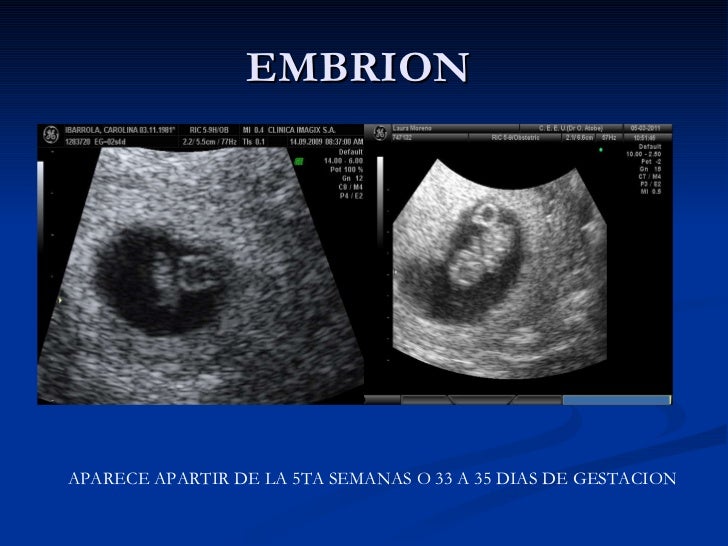

A la sexta semana, es cuando empieza a verse el embrión, pero el hecho de que aún, en su caso, no se vea no quiere decir nada Como le he dicho, es la fecha en la que aparece, pero existen varios motivos por los que, aun siendo un embarazo normal, puede no verse a la seis semanasEl embrión de seis semanas de gestación mide 5 milímetros y se independiza del saco vitelino El tubo neural del bebé empieza a cerrarse a estas alturas del embarazo Por eso es tan importante que tones ácido fólico antes de la concepción, ya que a veces no sabes que estás embarazada en este periodo precoz de la gestación Embarazo de 6 semanas en 2D y 3D Ecografías 2D (A) yLa semana 6 de embarazo es importantísima El latido del corazón del bebé se ve muy claro en la ecografía y su tubo neural ya empieza a cerrarse De ahí la importancia de la suplementación de ácido fólico en el embarazo La gestante empieza a notar claramente todos los síntomas de embarazo náuseas, vómitos, ganar constantes de orinar, cambios en el pecho, e incluso algunos